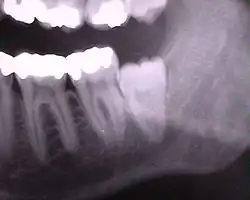

Eine Zahnretention (von latein: retinere ‚zurückhalten‘)[1] liegt vor, wenn ein Zahn im Kiefer eingeschlossen bleibt und nicht durchbricht, obwohl er oder sein Keim an der nahezu richtigen Stelle liegt.

Infolge Platzmangels retinieren insbesondere Weisheitszähne und obere Eckzähne (Man spricht hier auch von Impaktion). In der Häufigkeit folgen dann mit weitem Abstand die unteren Prämolaren. Überzählige Zähne (siehe Hyperdontie und Mesiodens) sind hingegen sehr häufig retiniert. Eine Retention von Milchzähnen hingegen ist selten.[2]

Hat der retinierte Zahn einen Milchzahnvorgänger, wird dessen Wurzel oft nicht resorbiert (aufgelöst) und der Milchzahn bleibt deshalb erhalten.